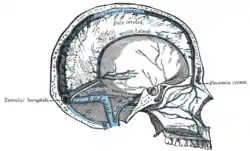

Sagittal section of the skull, showing the sinuses of the dura. (Cerebral veins labeled at center left.) | |

In human anatomy, the cerebral veins are blood vessels in the cerebral circulation which drain blood from the cerebrum of the human brain. They are divisible into external (superficial cerebral veins) and internal (internal cerebral veins) groups according to the outer or inner parts of the hemispheres they drain into.

The external cerebral veins known as the superficial cerebral veins are the superior cerebral veins, inferior cerebral veins, and middle cerebral veins. The superior cerebral veins on the upper side surfaces of the hemispheres drain into the superior sagittal sinus.[1] The superior cerebral veins include the superior anastomotic vein.